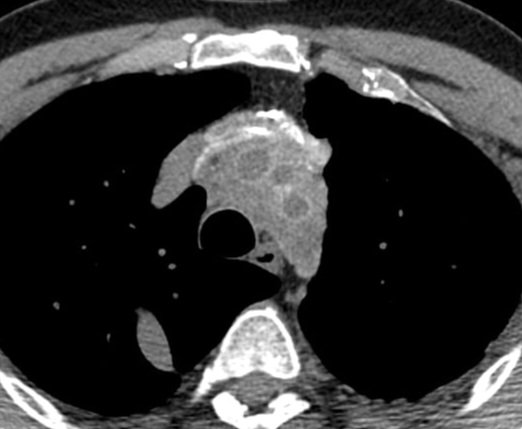

New @AJR_Radiology Accepted Manuscript: "Artificial Intelligence–Assisted Lung Nodule Evaluation on Low-Dose Chest CT in Asymptomatic Individuals: A Prospective Randomized Controlled Trial" By Drs Hwang, Goo, & team @snuh_official ajronline.org/doi/10.2214/AJ…